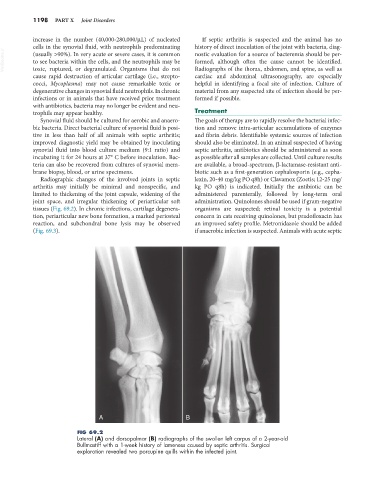

FIG 69.2

Lateral (A) and dorsopalmar (B) radiographs of the swollen left carpus of a 2-year-old

Bullmastiff with a 1-week history of lameness caused by septic arthritis. Surgical

exploration revealed two porcupine quills within the infected joint.

Radiographic changes of the involved joints in septic lexin, 20-40 mg/kg PO q8h) or Clavamox (Zoetis; 12-25 mg/

arthritis may initially be minimal and nonspecific, and kg PO q8h) is indicated. Initially the antibiotic can be

limited to thickening of the joint capsule, widening of the administered parenterally, followed by long-term oral

joint space, and irregular thickening of periarticular soft administration. Quinolones should be used if gram-negative

tissues (Fig. 69.2). In chronic infections, cartilage degenera- organisms are suspected; retinal toxicity is a potential